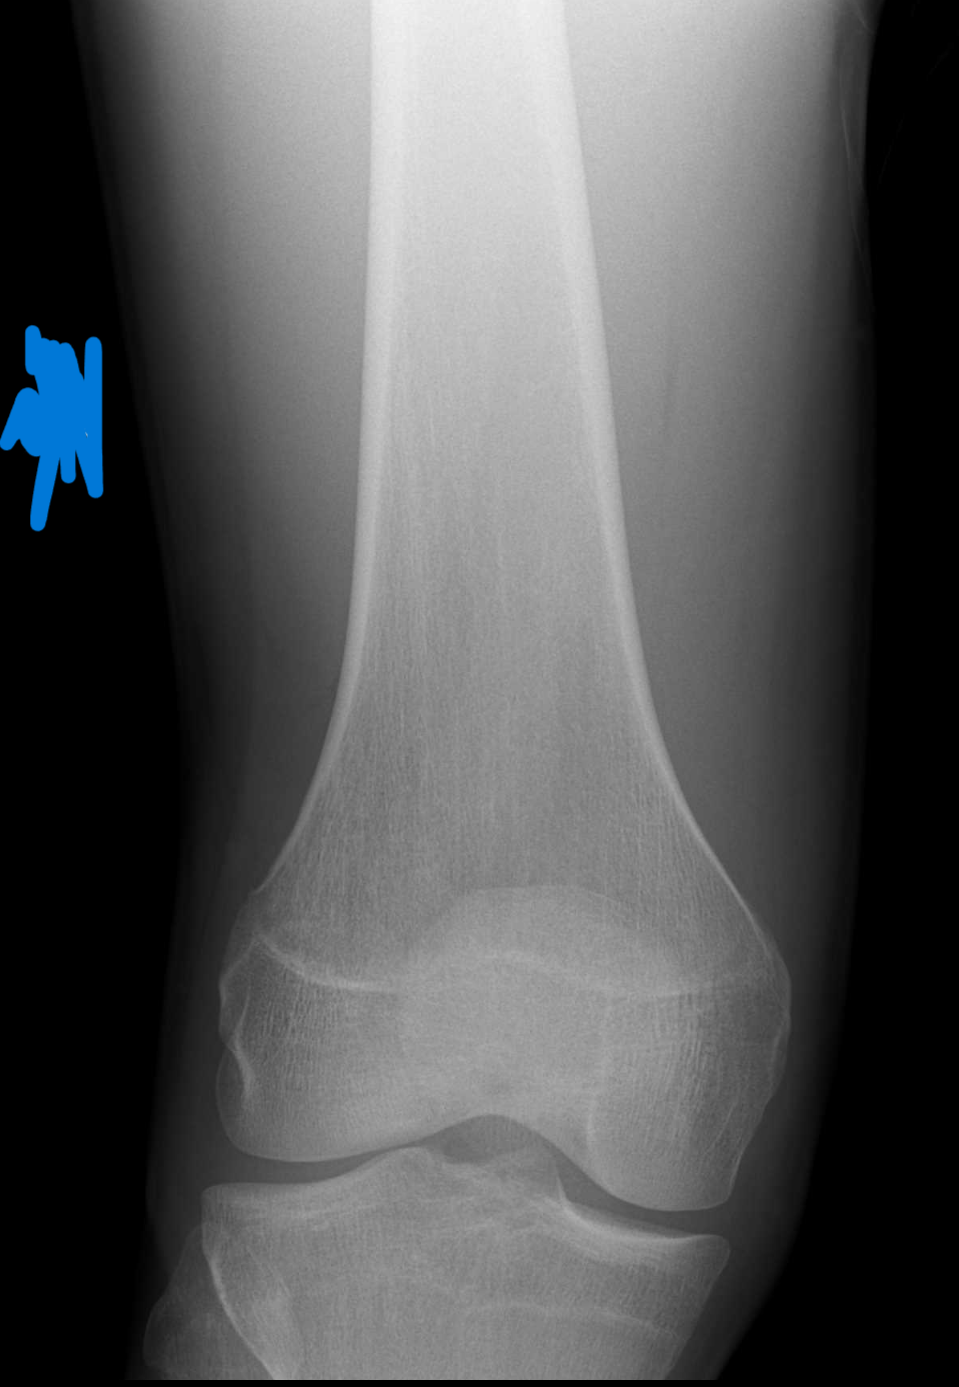

would it be worth getting on ai to try keep it open for as long as possible if it hasn't completely fused yet?They are technically fused. If u see a dark line, that is the translucent growth plate. A white line is the scar of the growth plate calcifying and turning solid. Every single doctor will tell you they're fused, but if u look really close, u can see faint dark streaks so theoretically you could maybe (maybe) have a tiny chance.

How late 17 are you? Like 17.5?View attachment 4390490View attachment 4390492 im 17 years old